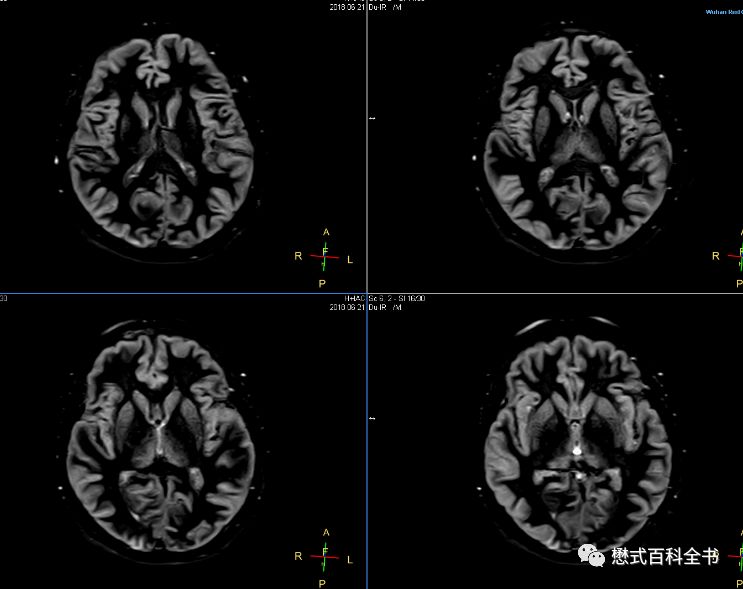

脑白质成像(White Matter only)序列TR=14489ms或者15000ms,大于14000ms,因为脑白质成像的TI时间不同;TE=25ms或者20ms;可以看出,脑白质成像序列的参数中,两个反转时间TI1和TI2都比脑灰质的长,所以自然脑白质成像序列的TR很长。而且根据经验,脑白质成像的扫描时间比灰质成像长,而且效果没有脑灰质好,仔细看会发现有一点勾边。这是无论如何怎么调都调不下去的。这和要选择性进行脑白质成像,选择的两个TI有关。

大家记住了这些参数后,自己在自家医院的MR设备上,都可以调出来。细心的老师还发现,虽然这个序列叫双反转,其实无论是脑灰质成像,还是脑白质成像,脂肪信号都被抑制掉了,可以先采用SPIR进行脂肪抑制。这样算下来的话,这个序列其实是一个准三反转序列(虽然SPIR反转的不是180°)。在血管壁或者心脏扫描中,为了彻底的抑制血液信号,也会采用双反转序列来达到黑血成像的目的。如果在黑血成像的基础上再进行脂肪抑制,则还需要提前施加一个反转脉冲对脂肪组织进行抑制,这样就组成了三反转序列。